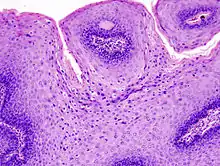

The diagnosis of genital warts is most often made visually, but may require confirmation by biopsy in some cases.[18] Smaller warts may occasionally be confused with molluscum contagiosum.[17] Genital warts, histopathologically, characteristically rise above the skin surface due to enlargement of the dermal papillae, have parakeratosis and the characteristic nuclear changes typical of HPV infections (nuclear enlargement with perinuclear clearing). DNA tests are available for diagnosis of high-risk HPV infections. Because genital warts are caused by low-risk HPV types, DNA tests cannot be used for diagnosis of genital warts or other low-risk HPV infections.[3]